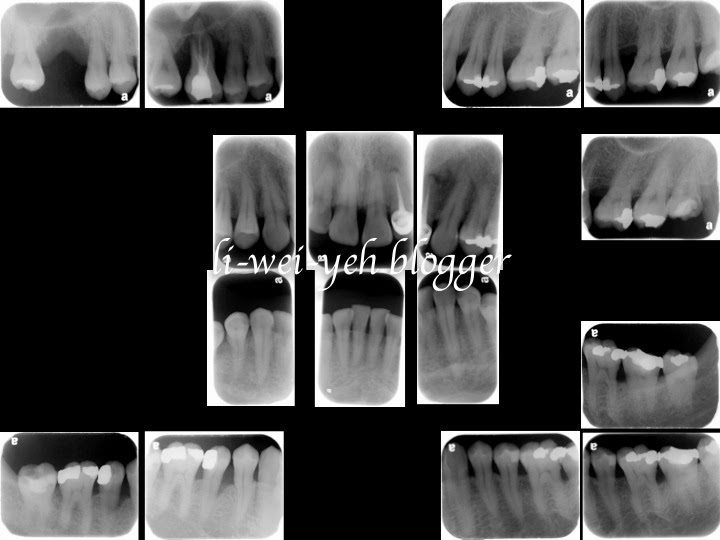

葉立維醫師分享右上第一大臼齒人工植牙案例(引導骨再生、鼻竇墊高術及游離牙齦移植術後)

手術部分:

右上側方開窗式鼻竇提升手術同時人工植牙

右上植牙二階段手術合併游離牙齦移植術